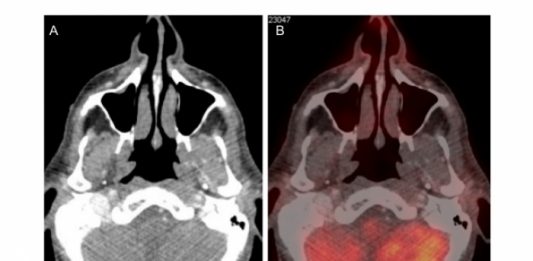

Rol del PET-CT en pacientes con Ataxia Cerebelosa

Es una técnica de diagnóstico innovadora que combina los beneficios de la medicina nuclear